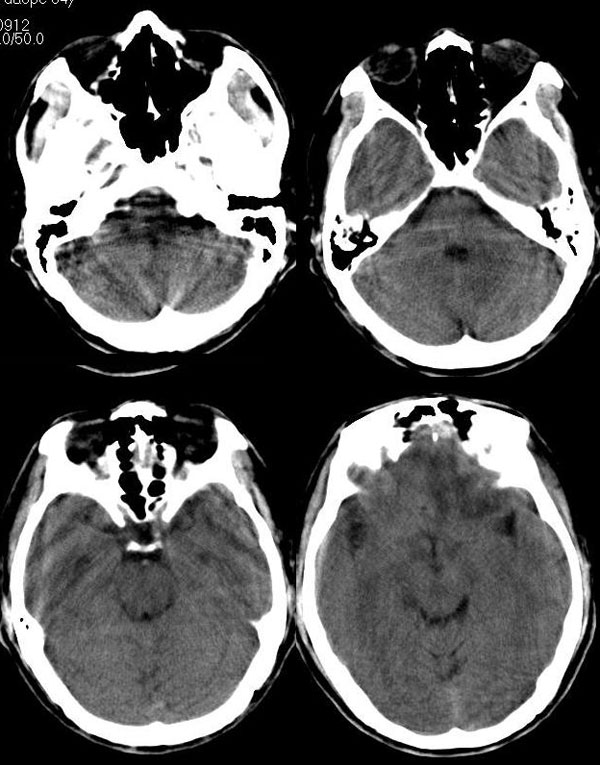

男 54岁 头痛,恶心,患者不同意增强扫描。

左额叶低密度病灶,其前上部分见等高密度影,占位征象明显,首先考虑胶质瘤。又有点象小结节大水肿的转移瘤表现,不知病史多长了,

左侧额叶白质区不规则略高密度影,周围见广泛水肿,左侧脑室受压变形,右侧额叶亦可见一小低密度影,多考虑转移瘤,建议肺部检查

首先考虑转移瘤,查找原发灶,先查肺部,右额叶是不是也有小病灶啊,如不做增强,可做mri。

双侧额叶等低密度灶 左侧有明显占位效应 考虑 转移瘤 可进一步mr检查确诊

左侧额叶不规则等、低混杂密度影,周围见广泛水肿,左侧脑室受压变形,右侧额叶亦可见一小低密度影,多考虑转移瘤,建议作mri检查

左额叶等、高混杂密度片块状病灶,灶周水肿明显,占位效应明显。单看此病灶的确象胶质母细胞瘤,但右额叶、四脑之左后部、脑干亦见数处大小不等片状低密度区,还是首先考虑转移瘤。

左侧额叶不规则略高密度影,周围见广泛水肿,左侧脑室受压变形,多考虑转移瘤,建议进一步检查查找原发灶。

强调前面的战友们提及到的,双侧额叶都有。